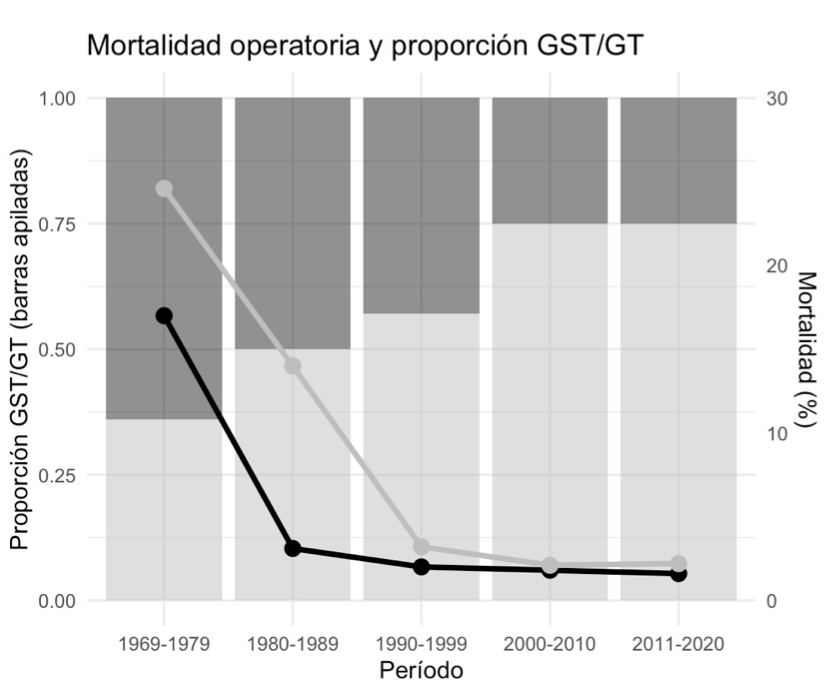

Bárbara Sofía Carreño Manríquez, Antonio Mercandino Sepulveda, Juan Ignacio Silva Bastias, Victoria Estrada Bobadilla, Matias Panza Csendes, Attila Csendes Juhasz

|

|

|